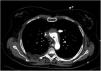

A patient is admitted to the hospital for an acute coronary syndrome complicated by a ventricular septal defect (VSD). Initially, treatment was performed with primary angioplasty and surgical correction of the VSD. During the procedure, the patient developed cardiogenic shock, requiring an intra-aortic balloon pump and a VA-ECMO. The VSD persisted despite treatment, leading to a heart transplant recommendation at a referral center. Prior to this, a CTA (computed tomography angiography) revealed an image consistent with an ascending aortic dissection (Images 1 and 2), resulting in the transplant being deferred. After reviewing the images at the transplant center, the aortic dissection was ruled out following assessment by transesophageal echocardiography of the aortic arch (Image 3), determining that the image was due to the confluence of ECMO flows, which eventually allowed the transplant to be performed.